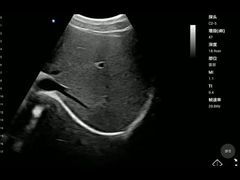

qualité Scanner tenu dans la main d'ultrason, Sonde sans fil d'ultrason fabricant de Chine

fournisseur de qualité Produits principaux